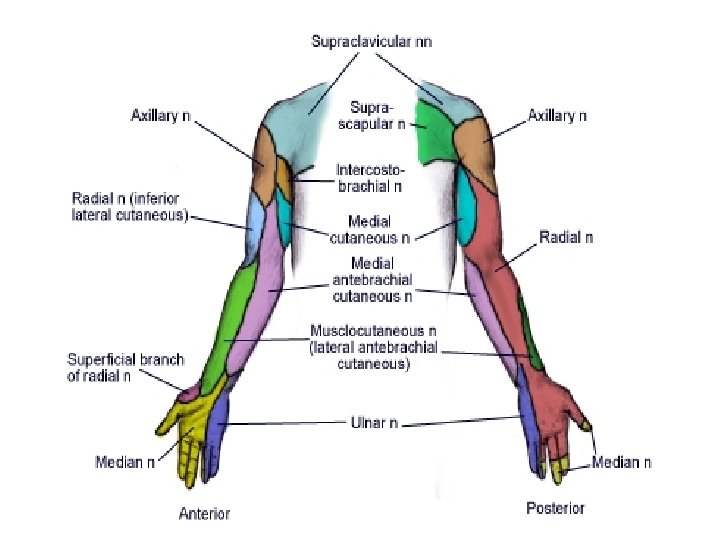

Upper extremity Interscalene Supraclavicular Infraclavicular Axillary

Brachial plexus anatomy • The brachial plexus extends from C 5 to T 1; (C 5, C 6, C 7, C 8 and T 1). • It innervates the shoulder and arm. • The brachial plexus begins as spinal nerve roots and continues to the terminal branches that supply the upper extremity. • Specifically, the anatomy progresses from roots to trunks, trunks to divisions, divisions to cords (lateral, medial and posterior cords) and finally to terminal nerve branches

Brachial Plexus Nerves